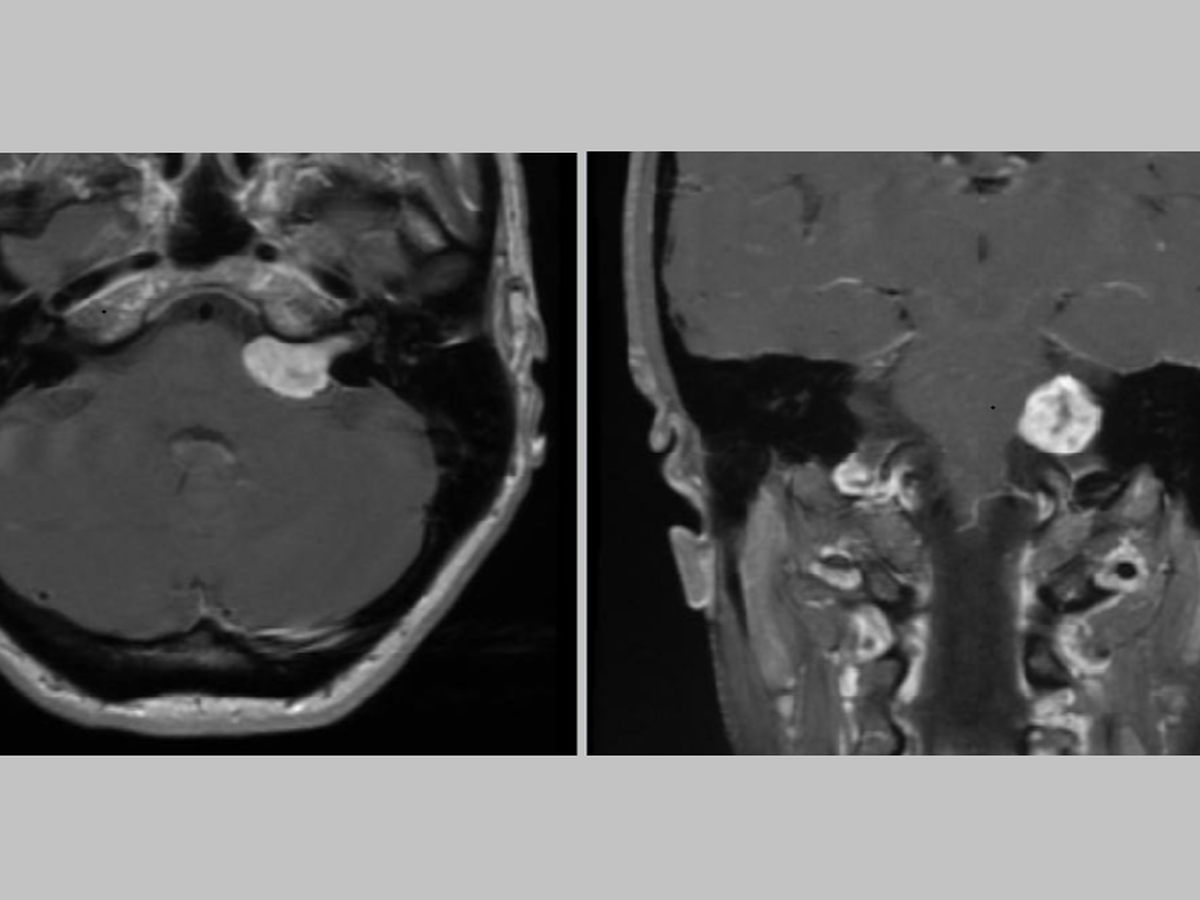

Prior to the pandemic, I was diagnosed with a treatable skull-based tumor that's compressing blood vessels, nerves, the brain stem, and other critical structures. At the time, I was already struggling physically, emotionally and financially because of several chronic conditions that include rare ones.

The more serious chronic conditions have gone untreated for far too long. The tumor symptoms are worsening and making it harder for me to work. I was last told that it's growing faster than normal. I have no idea today how much it has grown since the last scans, which were performed more than a year ago.